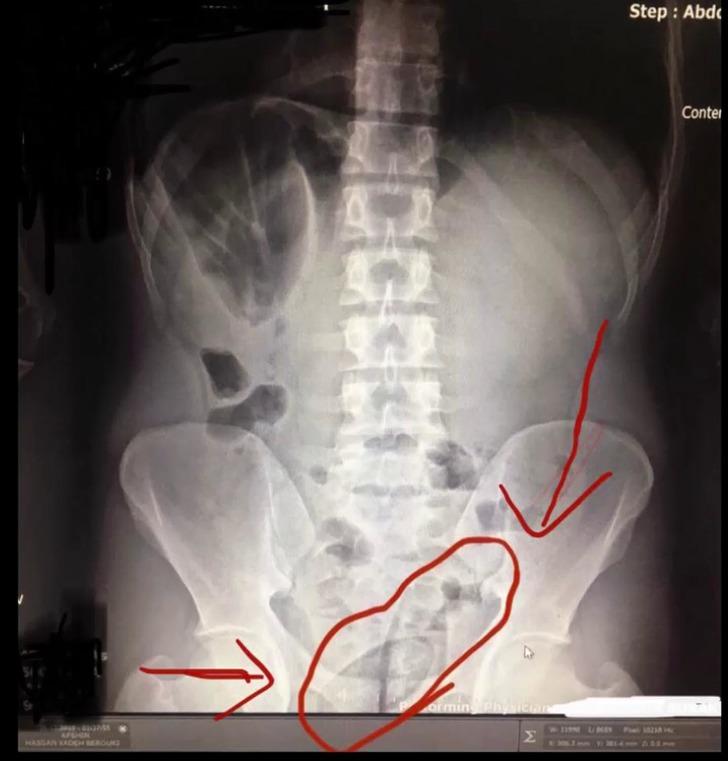

Kars'ta Narkotik Suçlarla Mücadele Şube Müdürlüğü ekiplerinin aldığı ihbar üzerine yaptığı operasyonda karşılaşılan durum 'pes' dedirtti. İran uyruklu iki şüphelinin doktor kontrolünde çekilen röntgenle ilginç bir gerçek gün yüzüne çıktı. Doktorlar tarafından çekilen röntgen sonucunda şüphelilerin bağırsaklarında kapsül içinde 150 gram metamfetamin ve 30 gram kubar esrar taşıdıkları öğrenildi.

GERÇEĞİ RÖNTGEN FİLMİ ORTAYA ÇIKARDI

Hastanede çekilen röntgen filminde, ikilinin bağırsaklarında kapsüller olduğu görüldü. İlaç verilerek doğal yollarla çıkmaları sağlanan kapsüllerde 150 gram metamfetamin ile 30 gram kubar esrar olduğu belirlendi. Narkotik polisi, A.H.Z.B., H.B. ve Türk vatandaşı E.A.'yı 'uyuşturucu ve uyarıcı madde ticareti' suçundan adliyeye sevk etti. 3 şüpheli tutuklanarak cezaevine gönderildi. (DHA)